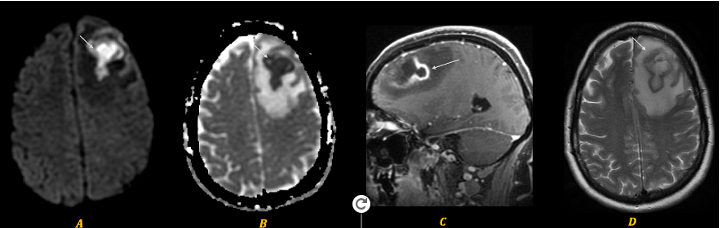

Sport-related concussion poses significant diagnostic challenges due to its subtle, transient nature and lack of identifiable biomarkers. To capture the changes from injury holistically, we integrated advanced neuroimaging with quantitative robotic assessment: Diffusion Tensor Imaging (DTI) and Neurite Orientation Dispersion and Density Imaging (NODDI) were used to detect acute microstructural white matter changes, while the Kinarm robotic platform objectively measured sensorimotor function via the Reverse Visually Guided Reaching (RVGR) task. This multimodal approach was applied to 12 concussed athletes (21 ± 2.1 y; 9 M/3 F; tested ~7 days post-injury) and 24 matched controls (21 ± 2.5 y; 11 M/16 F) to bridge structural and functional insights.

Significanttractswithsphere Noun slideshow grey Rvgrmethods

Behaviour (RVGR): Failed to detect functional deficits in the same acute period.

Screenshot 2025 05 30 at 11.49.38 pm

Neuroimaging (DTI/NODDI): Highly sensitive, revealing significant acute microstructural alterations in key white matter tracts.

Best correlation matrixnew page 0001

Conclusion

Our findings demonstrate that acute sport-related concussion induces detectable microstructural alterations in specific white matter tracts (↑FA, ↓MD/RD/Viso), yet these changes occur without concurrent deficits in sensorimotor performance on the precise Kinarm RVGR task. This critical disconnect underscores that advanced diffusion MRI (DTI/NODDI) is highly sensitive for detecting subclinical brain injury, revealing underlying pathology that standard functional assessments may miss. Consequently, relying solely on behavioural measures risks underestimating injury severity and compromising athlete safety. Multimodal assessment protocols, integrating both advanced neuroimaging and quantitative functional tools, are therefore essential for accurate diagnosis, informed return-to-play decisions, risk stratification, and targeted rehabilitation strategies following concussion.